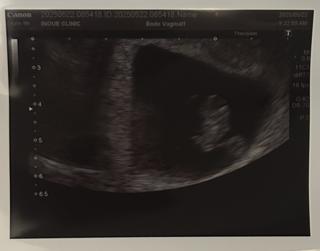

写真:8w3d:チョココロネさん

見方がよく分からないけど、心音聞こえました!